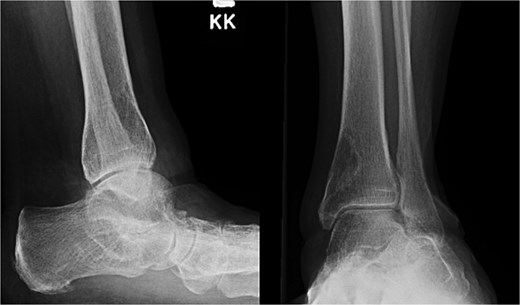

A 59-year-old woman with a medical history significant for rheumatoid arthritis treated with upadacitinib, hypothyroidism, depression, anxiety, and hypertension presented to the Emergency Department following a low-energy fall while walking, resulting in immediate left leg pain and inability to ambulate. Plain radiographs demonstrated a closed spiral fracture of the distal tibia with an associated proximal fibular fracture (Fig. 1). The limb was immobilized in a long-leg splint, and operative fixation was planned for the following day.

Preoperative anteroposterior and lateral radiographs of the left tibia and fibula demonstrating a spiral fracture of the distal tibial shaft with an associated proximal fibular fracture.